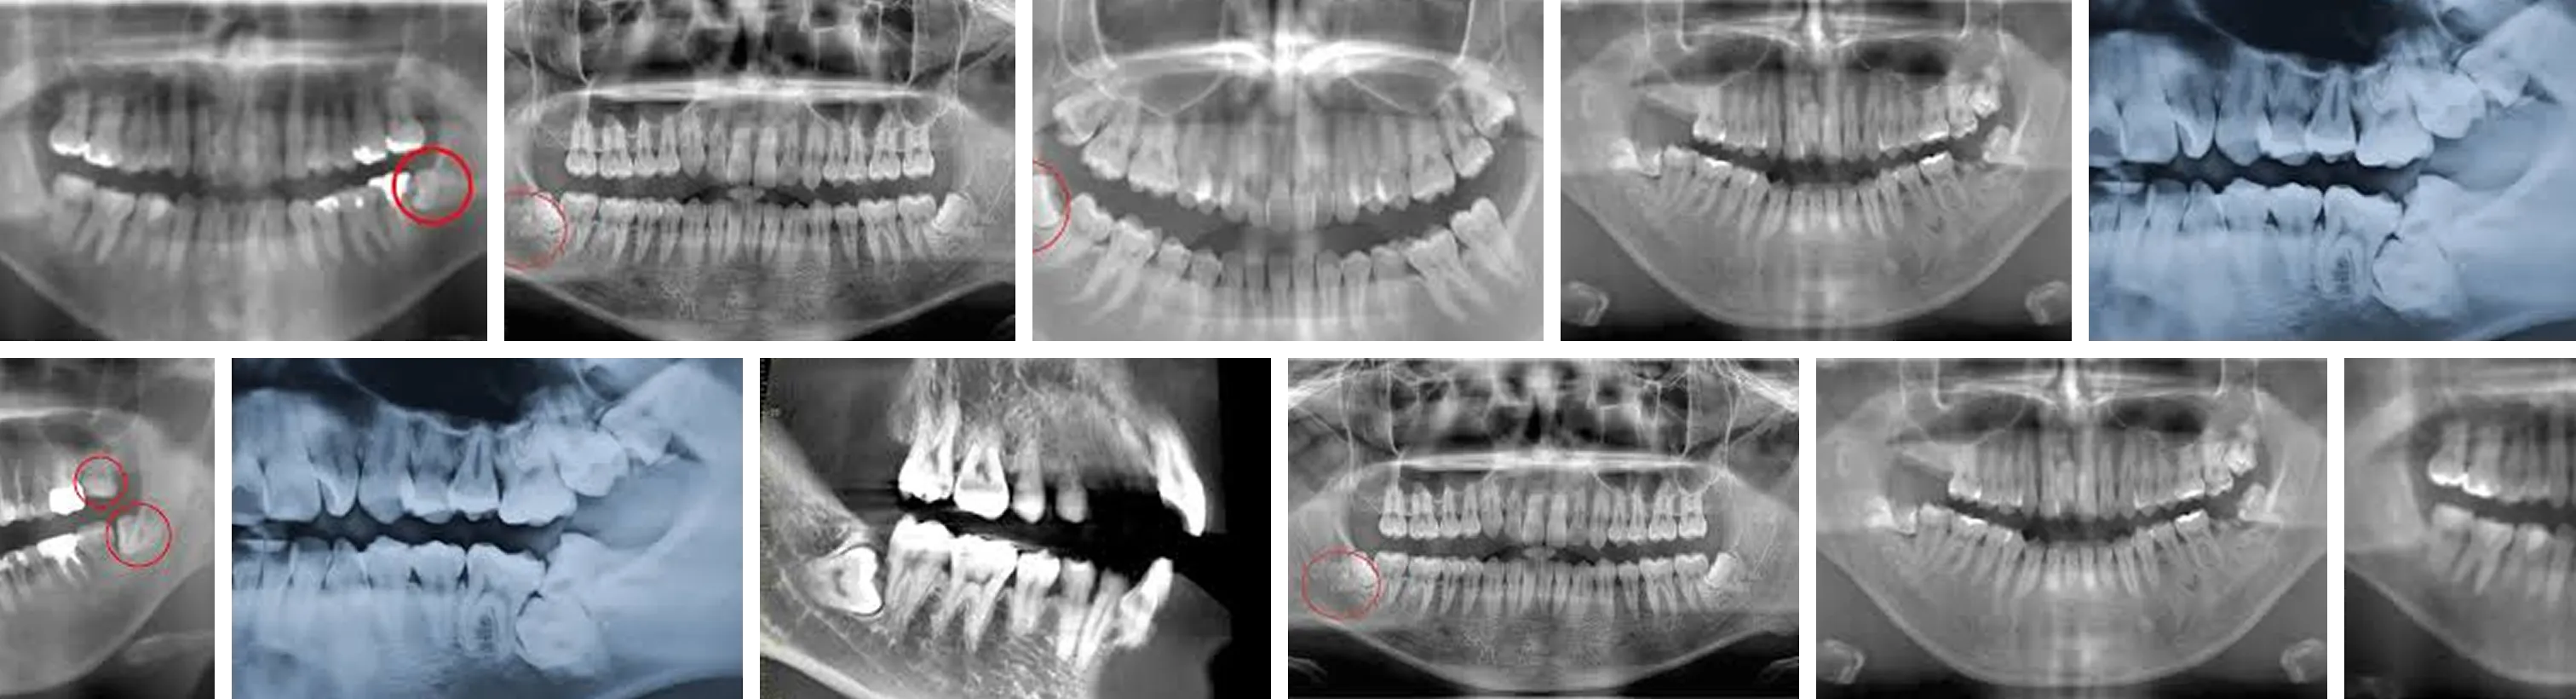

親知らず抜歯施術の様子

症例写真